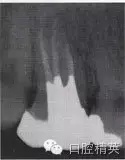

患牙根管的數(shù)目、位置以及根管的彎曲度和彎曲方向,也是影響外形制備的重要因素。為了使根管預(yù)備器械在無干擾的情況下進(jìn)入每一個根管,洞壁經(jīng)常被延長,入口的外形就隨之發(fā)生改變(圖4-2、3)。

圖4-3 延長洞壁的病例

A.術(shù)前X線片

B.洞壁被延長

C.根充及全冠修復(fù)